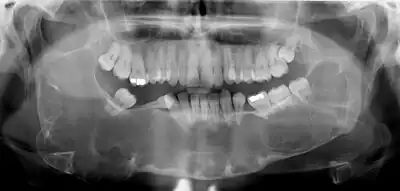

Diagnosis is usually radiological. However, definitive diagnosis is through biopsy. Aspirational biopsy of odontogenic keratocysts contains a greasy fluid which is pale in colour and contains keratotic squames.[12][2] Protein content of cyst fluid below 4g% is diagnostic of odontogenic keratocysts.[2] Smaller and unilocular lesions resembling other types of cysts may require a biopsy to confirm the diagnosis.[9] On a CT scan, the radiodensity of a keratocystic odontogenic tumour is about 30 Hounsfield units, which is about the same as ameloblastomas. However, ameloblastomas show more bone expansion and seldom show high density areas.[13]

Radiographs of odontogenic keratocysts show well-defined radiolucent areas with rounded or scalloped margins which are well demarcated.[12] These areas can be multilocular or unilocular. The growth pattern of the lesion is very characteristic from which a diagnosis can be made as there is growth and spread both forward and backward along the medullary cavity with little expansion. No resorption of teeth or inferior dental canal and minimal displacement of teeth is seen. Due to lack of expansion of the odontogenic keratocyst, the lesion can be very large when radiographically discovered.[9]